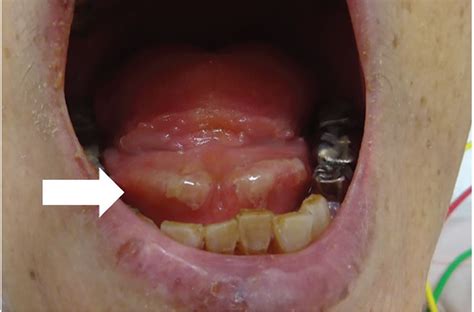

• Canker Sores (Aphthous Ulcers): These are small, painful, white or yellowish ulcers surrounded by a red area. They are not contagious but can be extremely sensitive to acidic or spicy foods.

Canker Sore White/Yellow center, red border 1–2 weeks